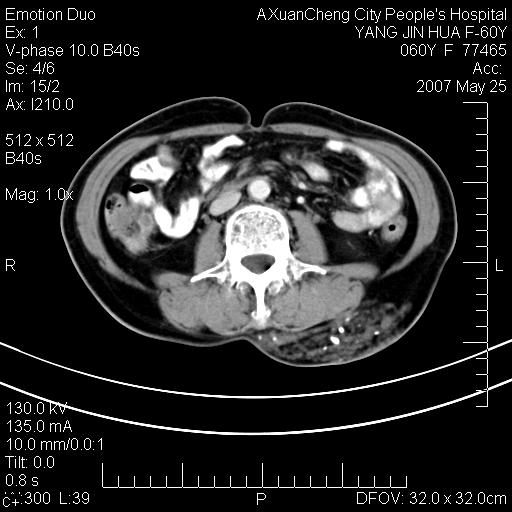

左背部皮下良性肿瘤,密度不均,边界不清,内有脂肪、钙化,增强扫描无明显强化,血管平滑肌脂肪瘤?进一步诊断有困难,建议穿刺活检。

这个病理增强扫描之前,我们是考虑是血管瘤,可是现在增强后一点强化都没有,还能考虑是血管瘤吗

左背部皮下良性肿瘤,密度不均,边界不清,内有脂肪、钙化,增强扫描无明显强化,血管平滑肌脂肪瘤?进一步诊断有困难,建议穿刺活检。还有,我想还是问一下病史,患者有外伤史吗?能否完全排除外伤后机化的....

血管平滑肌脂肪瘤,支持!另应详细了解病史,待除外骨化性肌炎。

1.考虑左腰部皮下平滑肌脂肪瘤可能性大;

2.位置特殊,不除外畸胎瘤及错构瘤可能;

3.另骨化性肌炎应在考虑范围之内,请追问病史;

还是考虑皮下血管瘤,强化不明显可能跟大量血栓形成有关,好多战友考虑血管平滑肌脂肪瘤,血管平滑肌脂肪瘤的血管就不强化么?只要有血管就都应该强化。